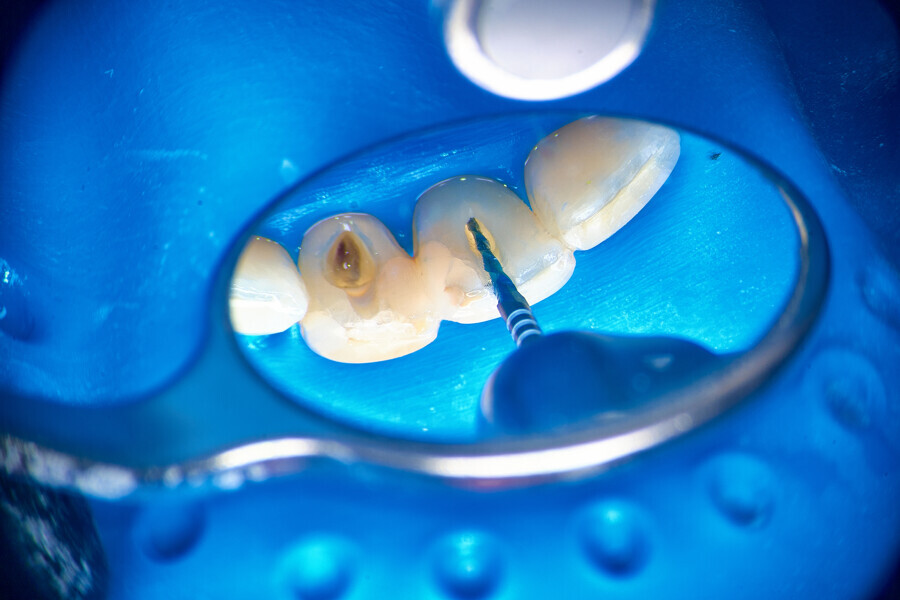

The piston technique is simple and predictable. Once the final preparation and irrigation protocol has been performed, owing to the specific properties of CSBSs, the canal should not be overdried. A small amount of moisture should remain in the canal space as the catalyst for the setting reaction of the sealer. With the application needle introduced to the maximum level of the insertion, gently eject the material from the syringe directly into the canal space. To avoid extrusion, try not to block the needle in the canal. After seeing the material in the canal space, remove the needle and use a hot gutta-percha extruder to create a plug in the coronal part. Next, push the coronal part of the gutta-percha with the cold plugger towards the apical zone. Do not push more than 1–2 mm (Fig. 1).